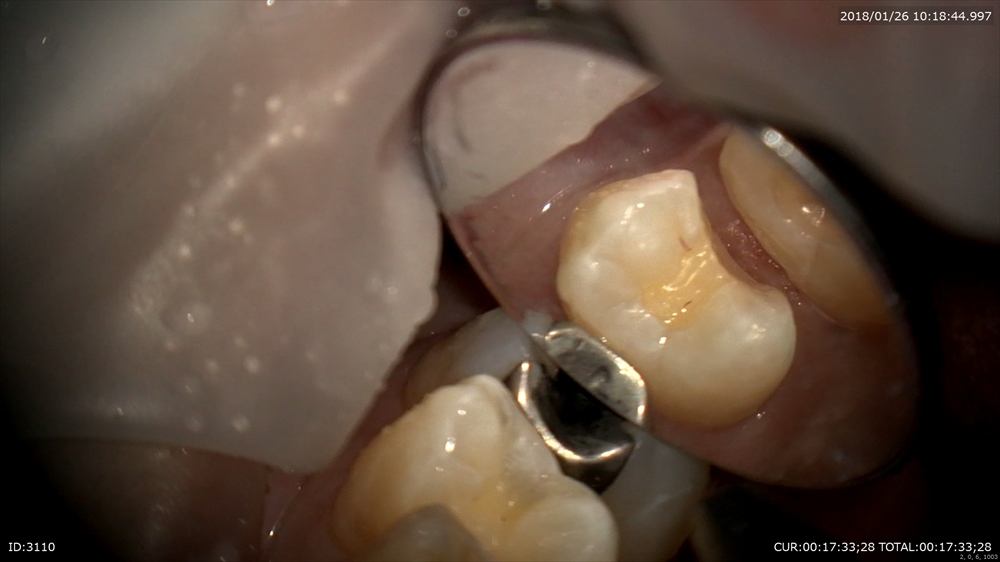

むし歯は大体中で広がります。 検知液で確認

綺麗にして型取り。次回で終わりです!